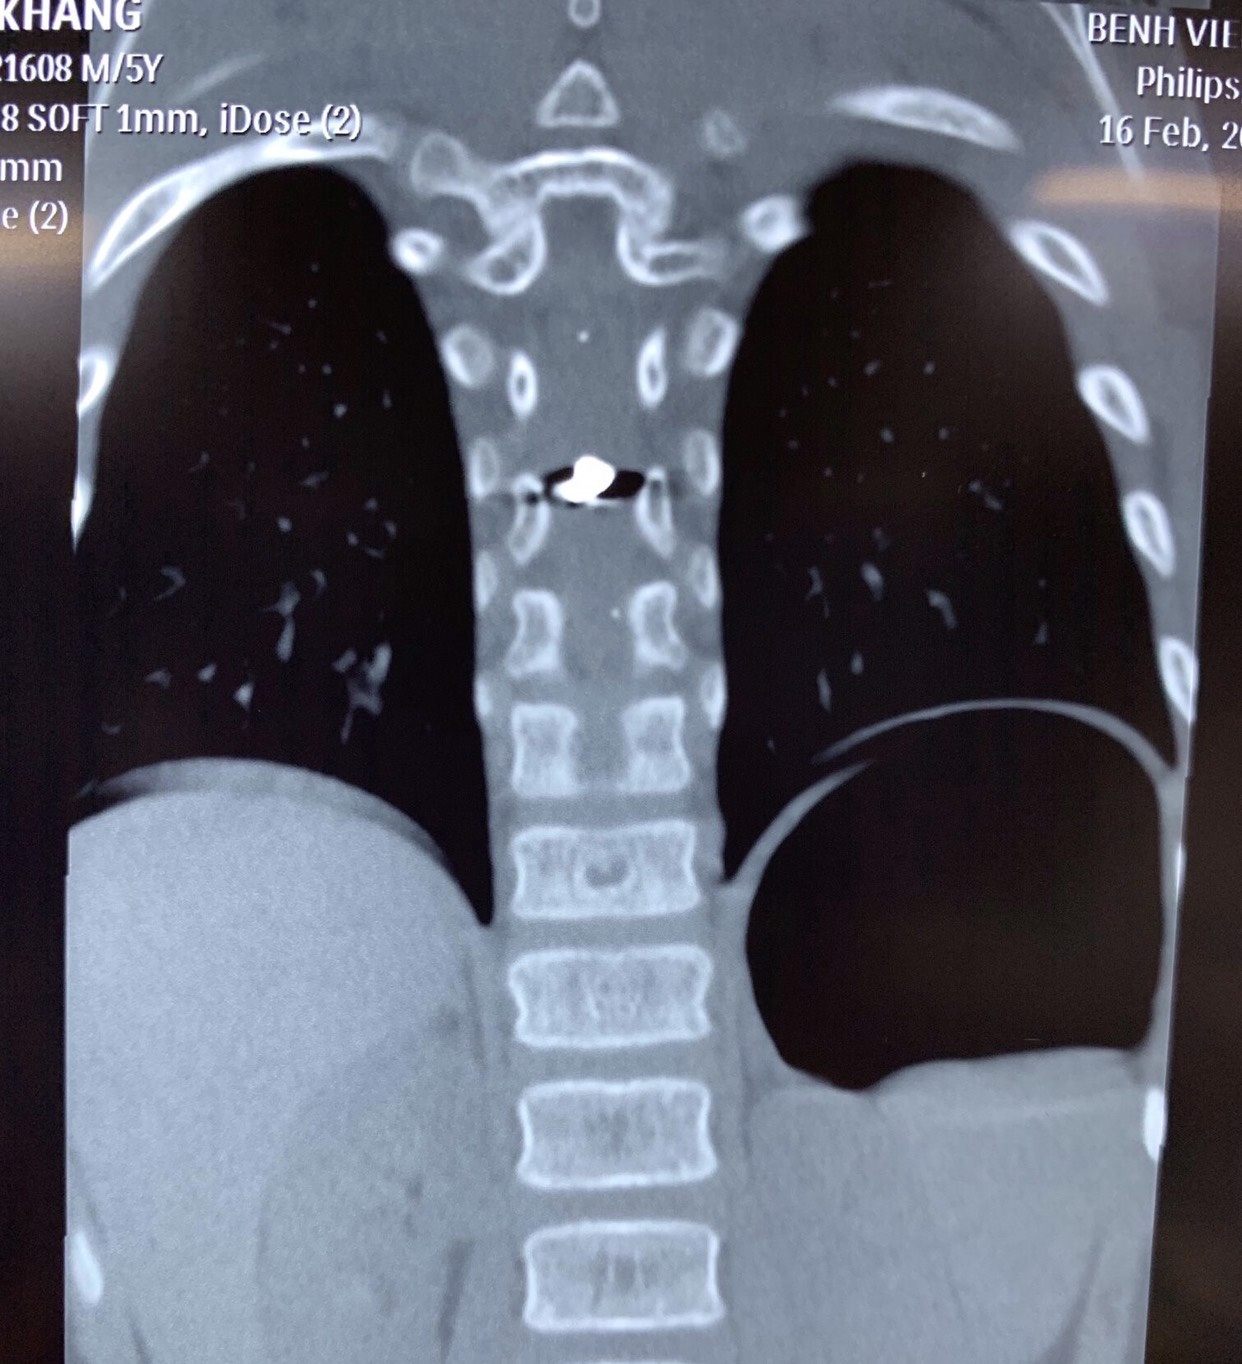

Hình ảnh viên đạn trong tuỷ sống bệnh nhi. Ảnh: BVCC.

Tại Bệnh viện Nhi Đồng 2, em được chụp CT Scan ngực, làm các xét nghiệm tiền phẫu.

Kết quả trên phim CT Scan cho thấy viên đạn chì xuyên vào tuỷ sống ngực của bệnh nhi.